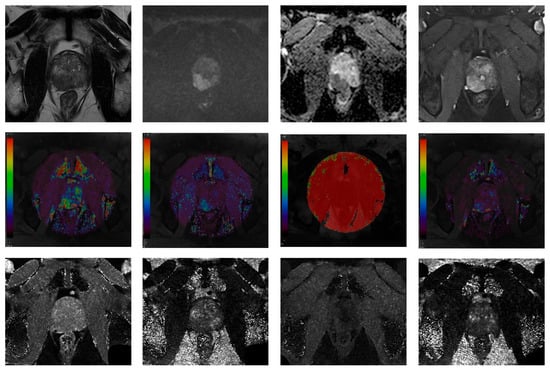

2.3. Image Analysis